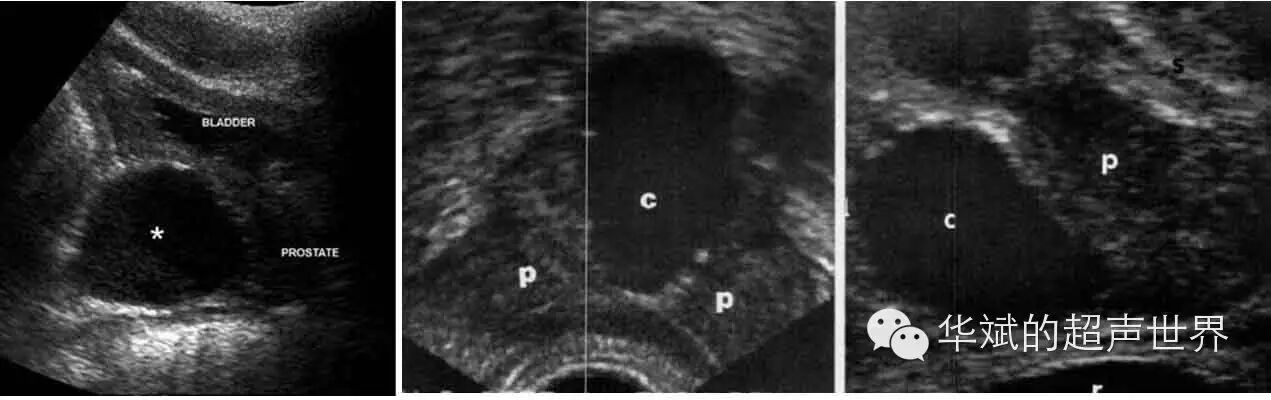

图2 苗勒氏管囊肿。囊肿为中线上,大部位于腺体外。左图;经腹部正中纵断,*:囊肿;中图:经直肠横断,C:囊肿,P:前列腺;右图:经直肠正中矢状断,C:囊肿,P:前列腺。